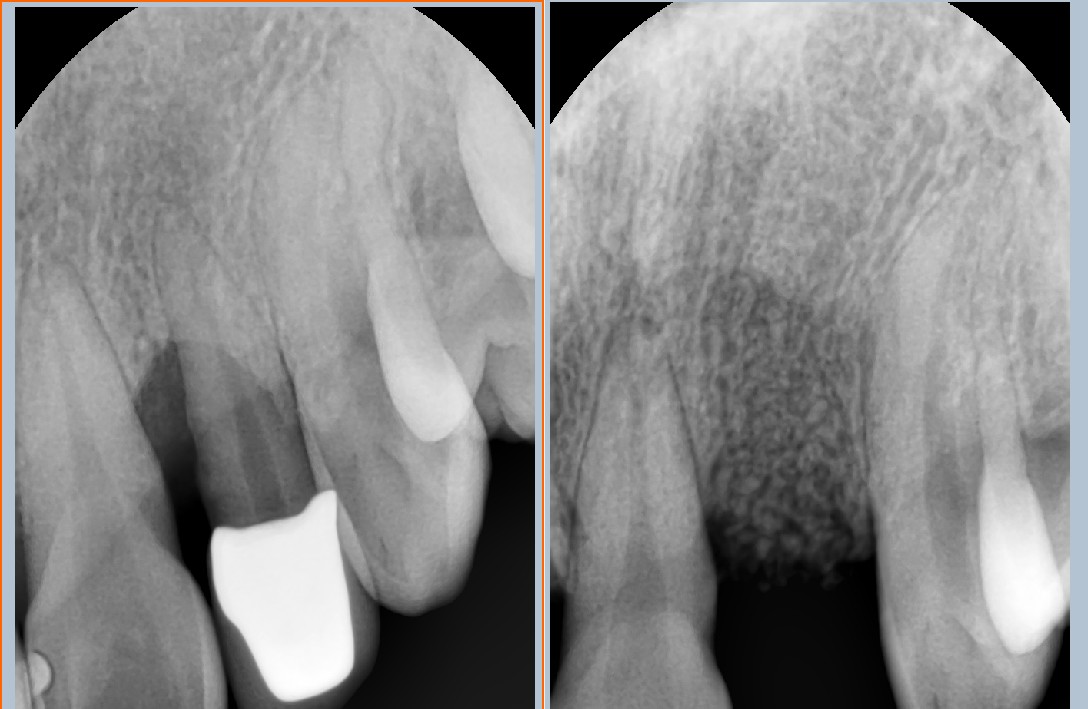

24³â 03 15ÀÏ ÀüÄ¡ºÎ½Ä¸³°í°ú °¡ÀÇÄ¡¸¦ ¸¸µé¾îÁÖ¾úÀ¾´Ï´Ù.

36¼¼¿© ȯÀÚºÐÀÔ´Ï´Ù.1¿ù¿¡ ¸¹ÀÌ Èçµé¸®°í »ÀÀÇ Èí¼ö°¡ ½ÉÇØ °ñÀ̽ĸ¸ ÇØ ³õ°í ÀÕ¸ö°ú °ñÁ¶Á÷À̾î´ÀÁ¤µµ Çü¼ºµÇ¾î ÀÓÇÁ¶õÆ®¸¦ ½Ä¸³ÇÏ¿´À¾´Ï´Ù.